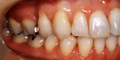

●主 訴 ― 叢生

●治療期間 ― 約5ヶ月

●治療内容 ― 上顎舌側、下顎唇側矯正装置、及びヘミオステオトミーによるスピード矯正(抜歯ケース) |